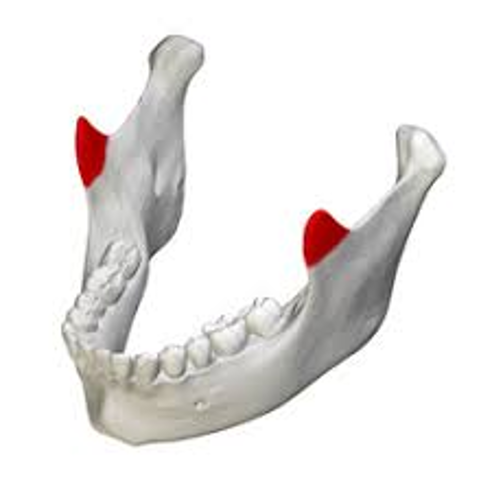

18

Q

What is this a picture of and what is it? What is an Example?

A

Process- Obvious prominence or projection of bone

ex. coronoid process of mandible